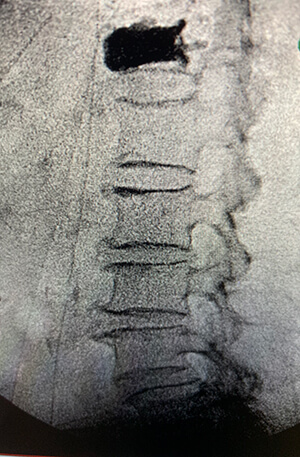

- Spinal X rays

- CT scan

- MRI scan